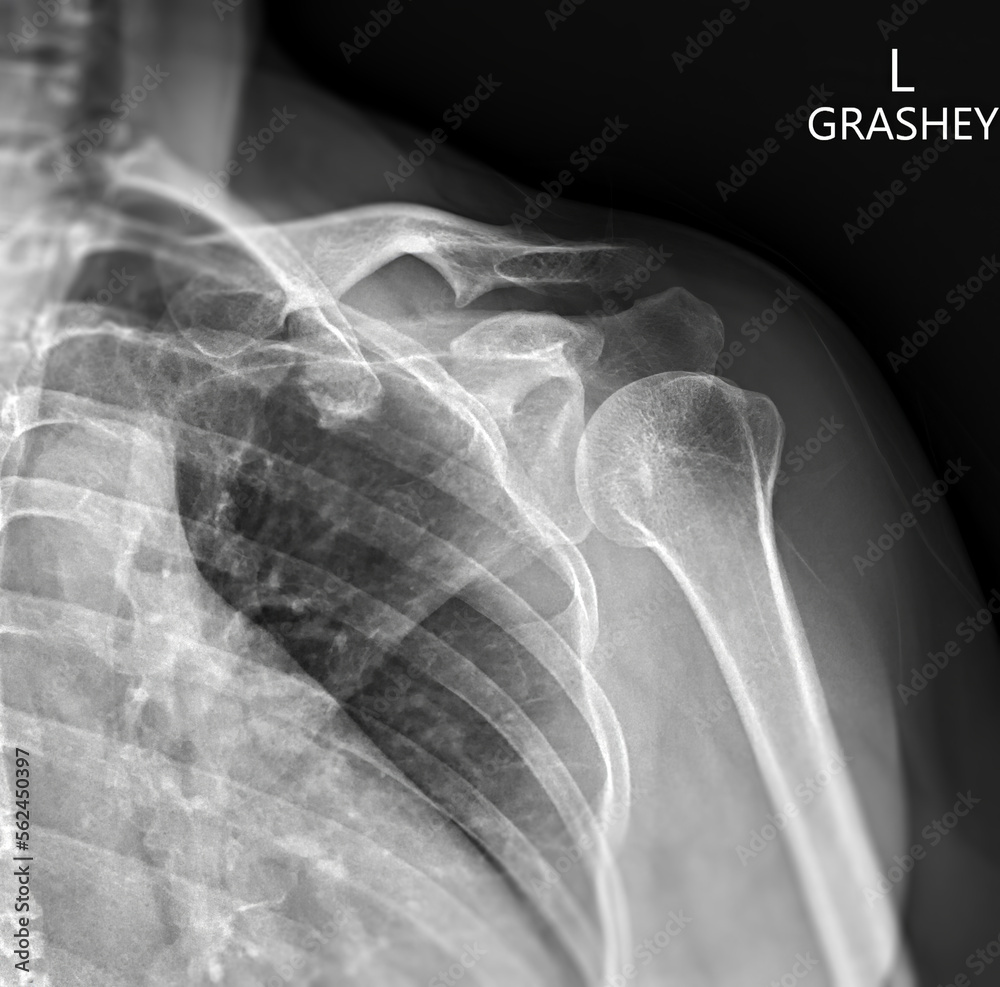

Рентген плеча: примеры снимков и их расшифровка